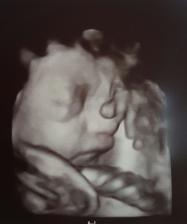

Gratuluji, je to veliký zázrak!!🙂 Z ničeho je malý tvoříček!! 🙂 už se těšíme na druhé,l ale ješte si poškáme, termín máme 01.01.2017